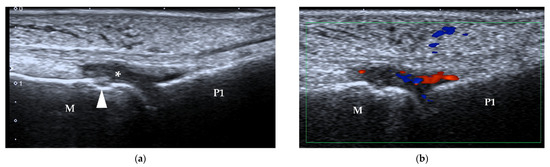

| Sesamoiditis | / | blurred sesamoid bone cortex, with or without cortical disruption and surrounding soft tissue edema |